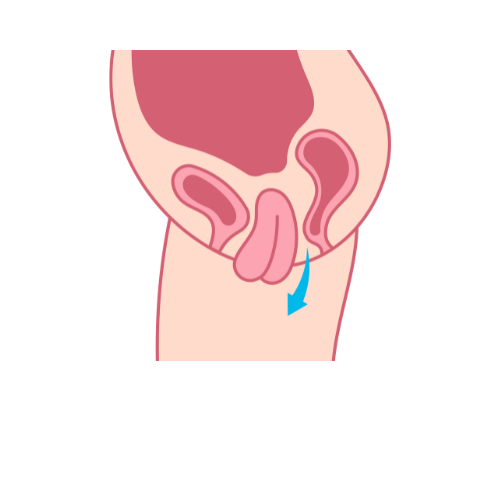

Pelvic Organ Prolapse (POP)

Our gynecologist provides specialized care for pelvic organ prolapse, offering comprehensive evaluations and personalized treatments to restore pelvic support and improve overall reproductive health.